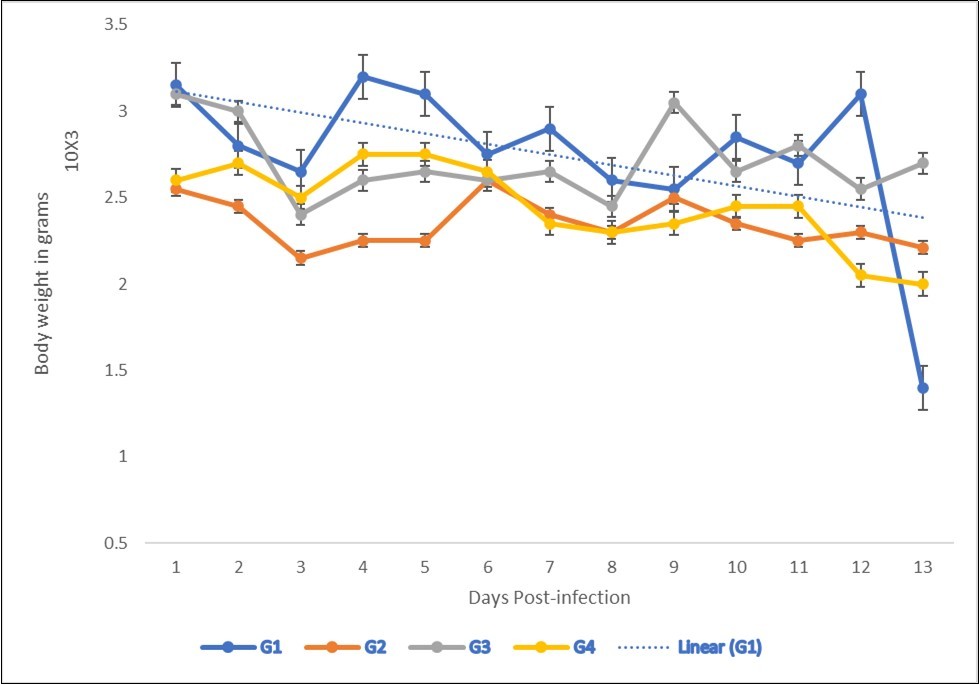

The Effect of NeemAzal® on Oocyst Count and Weight Gain (Efficacy Study) at a dose of 200mg/kg birds treated with NeemAzal® a statistically significant (P≤0.05) increase in weight gain was recorded among treated groups (Figure 1 & Figure 2). During the first 3 days of infection, there was no fecal output of oocysts. On day5 p.i., the output differed between NeemAzal® treated and non-treated chickens. In the latter, the number of excreted oocysts reached approximately 1.3×105 per gram feces (Figure 2).

Figure 2.Effect of NeemAzal®Oil treatment on Body weight gain of Broiler Chicken infected with Eimeria tenella oocysts. G2=negative control (infected, not treated). G3=positive control (infected and treated with amprolium) 13 days’ post-infection